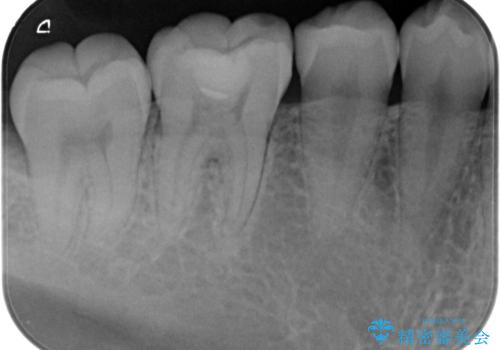

- 樹脂の材料での治療をセラミックに変えたいとの事で来院。

拡大鏡下で古い樹脂を除去し、虫歯がない事を確認してe-maxインレーで治療を行いました。

適合の良い詰め物が入りました。